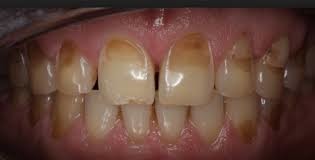

The signs of enamel erosion can vary, depending on the stage. Some signs may include:

Sensitivity. Certain foods (sweets) and temperatures of foods (hot or cold) may cause a twinge of pain in the early stage of enamel erosion.

Discoloration. As the enamel erodes and more dentin is exposed, the teeth may appear yellow.

Cracks and chips. The edges of teeth become more rough, irregular, and jagged as enamel erodes.

Severe, painful sensitivity. In later stages of enamel erosion, teeth become extremely sensitive to temperatures and sweets. You may feel a painful jolt that takes your breath away.

Cupping. Indentations appear on the surface of the teeth.